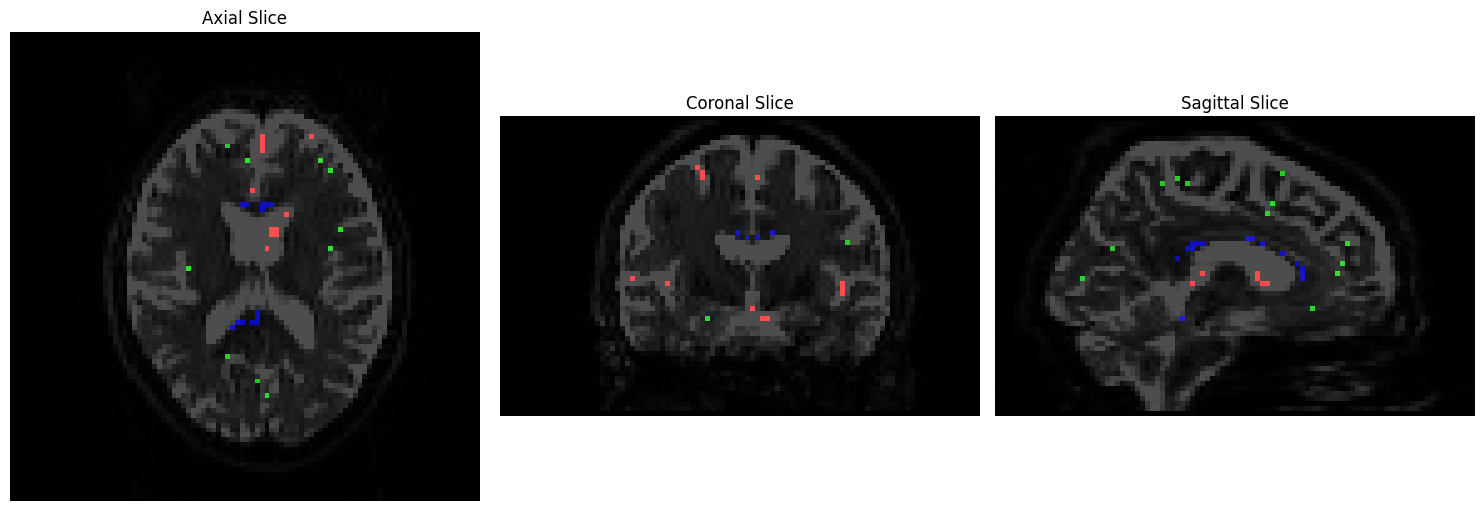

We will visualize the voxels used to construct a basis function for each tissue type using Matplotlib. CSF voxels should be colored red, gray matter voxels green, and white matter voxels blue:

# Prepare RGB overlay for tissue types

rgb_overlay = np.zeros(data2.shape[:3] + (3,), dtype=np.float32)

rgb_overlay[..., 0] = data2[..., 0] # Red for CSF

rgb_overlay[..., 1] = data2[..., 1] # Green for GM

rgb_overlay[..., 2] = data2[..., 2] # Blue for WM

# Plot the slices

fig, axes = plt.subplots(1, 3, figsize=(15, 5))

# Axial slice

axes[0].imshow(np.rot90(data1[:, :, slice_idx1, 0]), cmap="Greys_r", vmin=0, vmax=700)

axes[0].imshow(np.rot90(rgb_overlay[:, :, slice_idx1]), alpha=0.7)

axes[0].axis("off")

axes[0].set_title('Axial Slice')

# Coronal slice

axes[1].imshow(np.rot90(data1[:, slice_idx2, :, 0]), cmap="Greys_r", vmin=0, vmax=700)

axes[1].imshow(np.rot90(rgb_overlay[:, slice_idx2, :]), alpha=0.7)

axes[1].axis("off")

axes[1].set_title('Coronal Slice')

# Sagittal slice

axes[2].imshow(np.rot90(data1[slice_idx3, :, :, 0]), cmap="Greys_r", vmin=0, vmax=700)

axes[2].imshow(np.rot90(rgb_overlay[slice_idx3, :, :]), alpha=0.7)

axes[2].axis("off")

axes[2].set_title('Sagittal Slice')

# Adjust layout and display

plt.tight_layout()

plt.show()